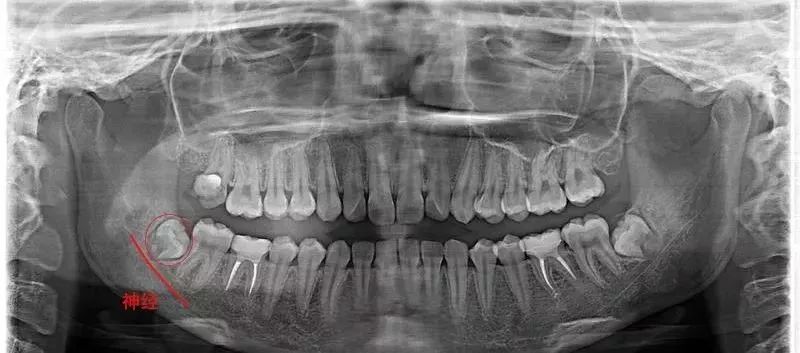

要不怎么建议大家高考完就去拔智齿呢,想想你十八九岁时,多数人的智齿牙根发育还未完全,这时候拔智齿既不会伤及神经,又赶在智齿把整齐的牙齿挤歪之前。

智齿刚萌出时的牙周膜时牙周膜对智齿“抓”得还没那么牢固,再加上周围骨质较松,拔牙时骨阻力较少。欣赏一下整齐的、牙根尚未发育完全的智齿↓

医生拔得轻松,你也恢复得更快。18岁的牙根 vs 28岁的牙根↓